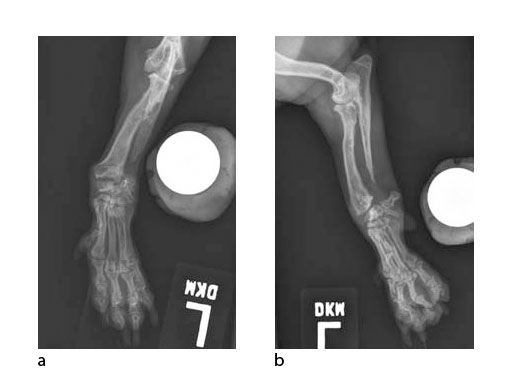

A 5-year-old female 3.5 kg dachshund with bilateral carpal hyperextension secondary to erosive polyarthroplathy (rheumatoid arthritis) (Fig 3, Fig 4) was treated bilaterally with a staged pancarpal arthrodesis with straight LCPs. The right carpus was operated first and healed in 10 weeks. The left carpus was operated 5 months after the initial surgery (Fig 5). Complete healing was noted 3 months postoperatively (Fig 6).